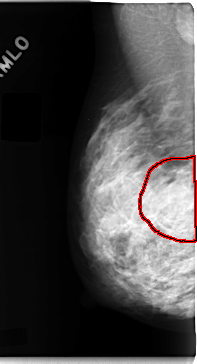

C_0098_1.RIGHT_MLO

RIGHT_MLO LINES 4720 PIXELS_PER_LINE 2560 BITS_PER_PIXEL 12 RESOLUTION 50 OVERLAY

FILE: C_0098_1.RIGHT_MLO.OVERLAY

TOTAL_ABNORMALITIES 1

ABNORMALITY 1

LESION_TYPE MASS SHAPE IRREGULAR MARGINS ILL_DEFINED

ASSESSMENT 4

SUBTLETY 2

PATHOLOGY MALIGNANT

TOTAL_OUTLINES 1

BOUNDARY